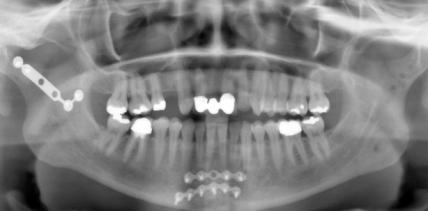

articleImage

Cosmetic Dentistry 28.02.2011

Individualästhetik in der Gesichtschirurgie

Differenzierte Operationsverfahren zur Verjüngung der Stirn-, Augenbrauen- und Oberlidregion Ästhetische Operationen sind eine Domäne der Mund-, Kiefer- und Gesichtschirurgie. Das Behandlungsziel klingt einfach und ist zugleich überaus anspruchsvoll: gutes Aussehen und ein schönes individuelles Gesicht im Zusammenhang des harmonischen Ganzen von Körper, Geist und Seele. Ob die MKG-Chirurgen mit ihrer Behandlung dieses Ziel zuletzt erreichen, dafür gibt es nur ein allgemein anerkanntes und weiterlesen